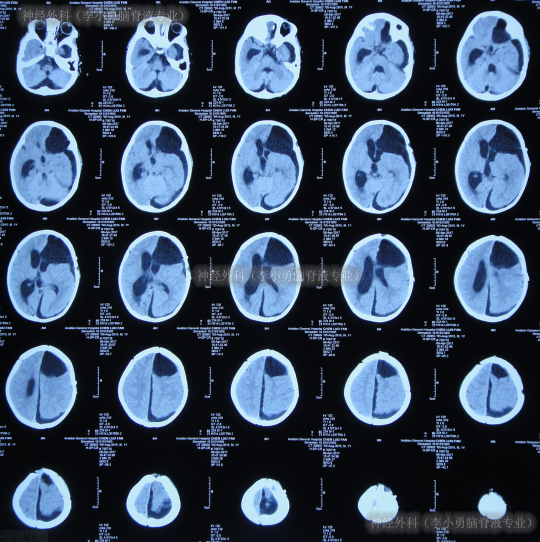

继续治疗1月的时间,期间患儿身体状态变得越来越好,情绪愉悦,肢体活动正常,期间2次查头颅CT均示脑室进一步缩小(图-21)。

图-21:2017年8月3日

2017年10月8日(李小勇脑脊液专业治80天)出院,出院时:精神状态好,肢体活动正常,能自己走路稍不稳,可简单言语交流;头围由入院时55cm缩小至51.5cm(图-22);出院时头颅CT示脑室分流术后状态,无异常(图-23)。

图-22:2017年10月8日

图-23:2017年10月8日头颅CT